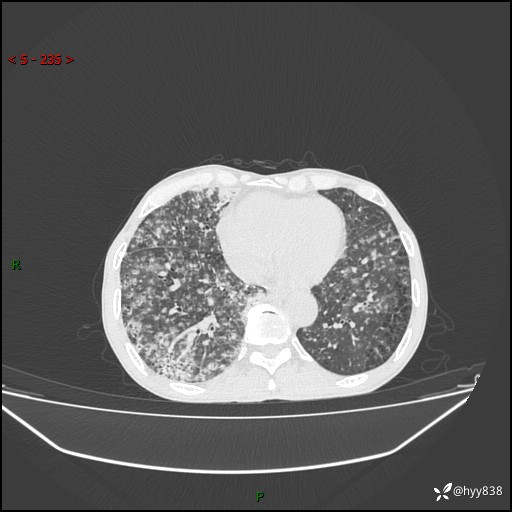

胸部CT平扫